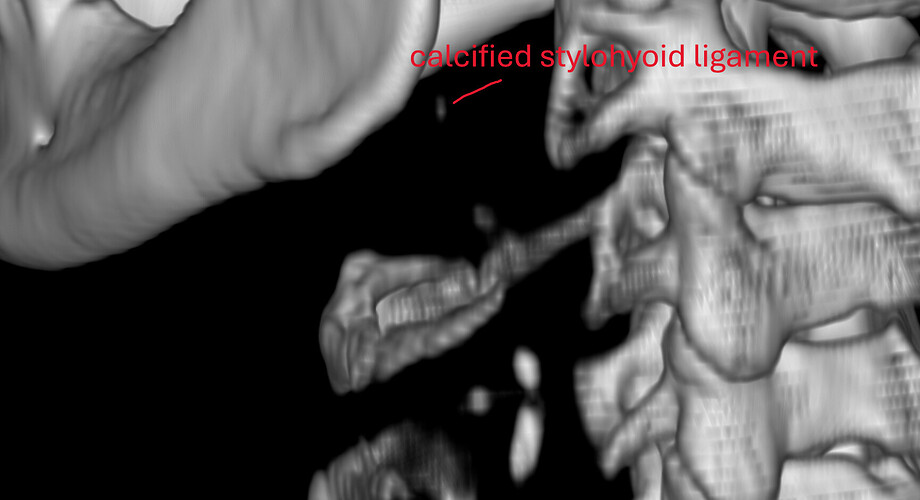

- Finally, my oral surgeon spotted something on the dental CBCT and asked me to check if I have ES. So, I did the CT for ES and it revealed a calcified portion of the stylohyoid ligament.

And, before we proceed, I literally looked at the 3D rendered CT today, and the calcified portion is only ~15mm, detached from styloid process, and about 1.5mm from C1. In the CT results, it says “partially calcified stylohyoid ligament, combined length 31mm” but the keyword there is “combined.”

Sagittal view. Calcified portion of stylohyoid ligament. There is a little bit more in another slice, but this is the most of it.

3D views – one is low-res from above CT, and another is high-res from a CT with 0.2mm slices (most detailed CT I’ve ever seen). Distance from C1 is measured at about 1.5mm, length of calcified portion is ~15mm and it is flatter on one side in the lower section, with a “bit” sticking out slightly.